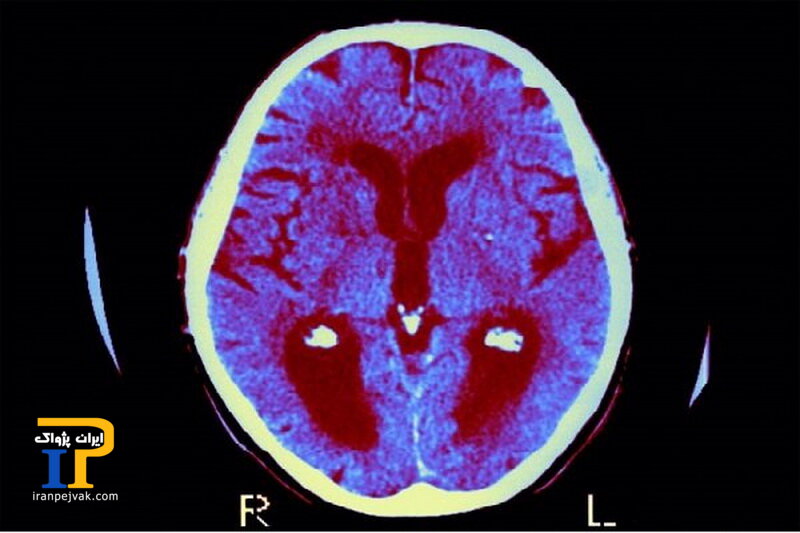

این مطالعه نشان داد که سطح بالاتر سرب خون بین سنین ۴ تا ۶ سال، حتی در سطوح نسبتاً پایین مواجهه، به طور قابل توجهی با سرعت بیشتر فراموشی مرتبط است، به طوری که میانگین سطح سرب خون تقریباً ۱.۷ میکروگرم در دسیلیتر است.

این یافتهها نشان میدهد که حتی مواجهه با سرب در سطوح پایین نیز میتواند عملکردهای شناختی حیاتی را در اوایل کودکی به خطر بیندازد.